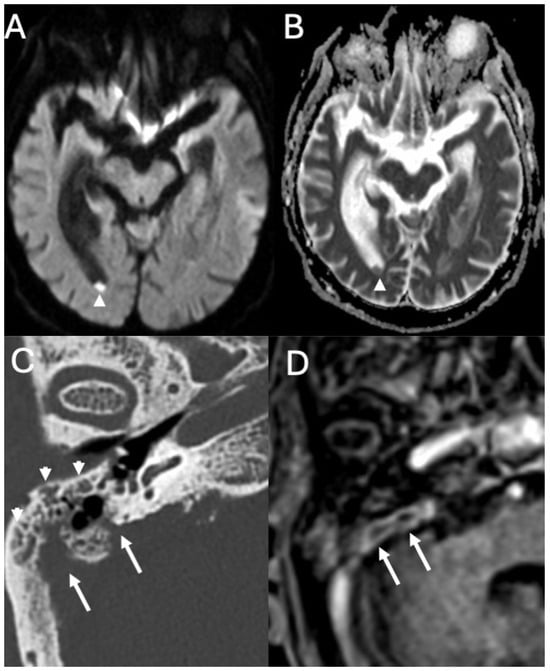

3.4. Labyrinthitis and Vestibulocochlear Neuritis

Imaging

| Labyrinthitis/Vestibulocochlear Neuritis | Taxak & Ram 2020 [32]; Kharrat et al., 2024 [33]; Singh et al., 2023 [34]; Kim et al., 2024 [35] | Case reports and small series | Meningitis can cause secondary labyrinthitis with cochlear enhancement on MRI; progression to ossification possible if chronic. |

| Cochlear Hemorrhage (Rare Complication) | Perillo et al., 2024 [36]; Engelen-Lee et al., 2016 [37] | Case report; pathologic correlation study | First documented case of cochlear hemorrhage secondary to pneumococcal meningitis; likely due to microvascular injury. |